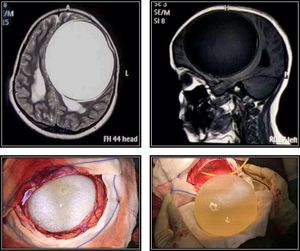

12-year-old girl with a tapeworm hydatid cyst half the size of her brain in her head